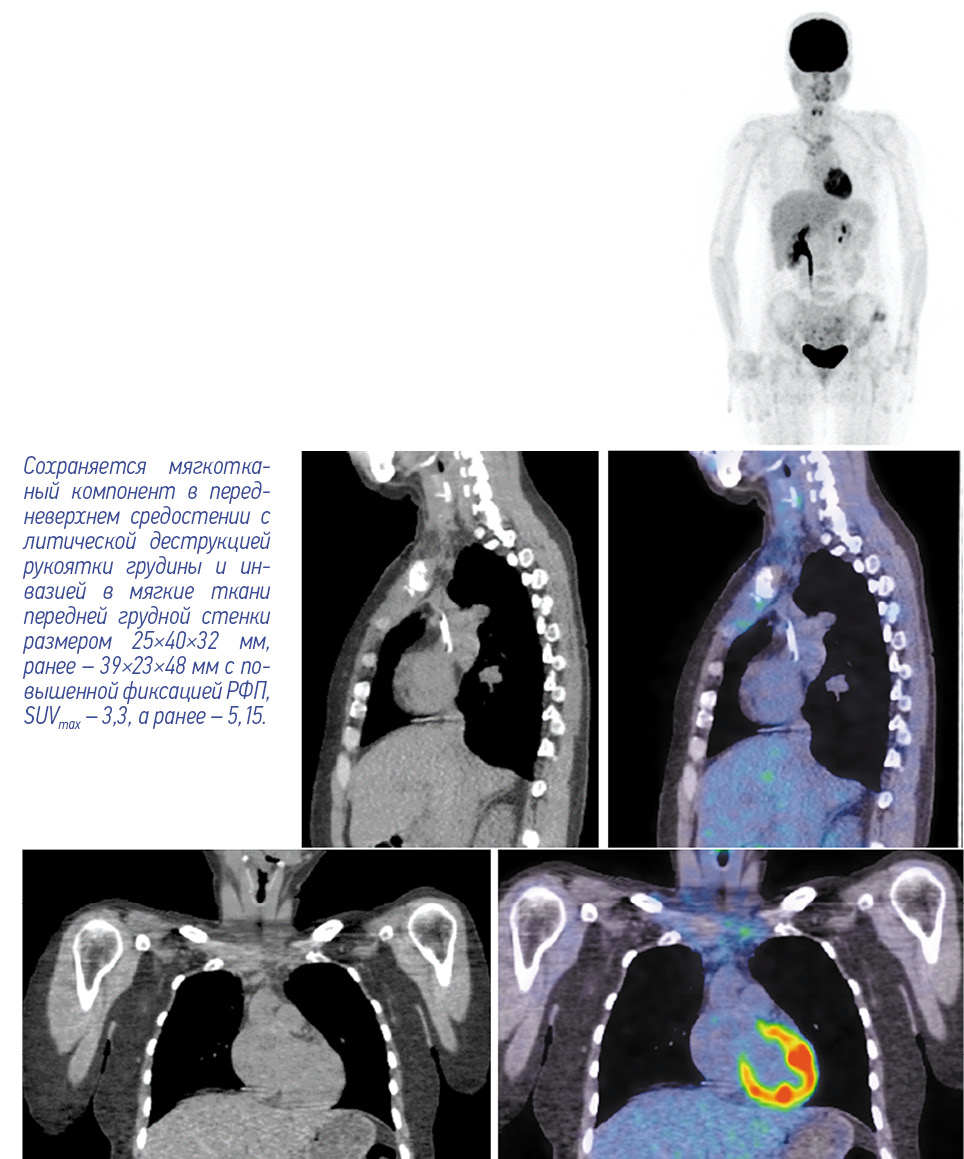

Согласно результатам ПЭТ/КТ, лимфоузлы шеи не увеличены, без повышенной метаболической активности. На уровне щитовидной железы патологически измененной ткани не определяется. Тем не менее в передневерхнем средостении имеется мягкотканый компонент с литической деструкцией рукоятки грудины и инвазией в мягкие ткани передней грудной стенки размером 40×32 мм по сравнению с 23×48 мм в предыдущем исследовании, с повышенной фиксацией РФП, SUVmax – 3,3 (рис. 3, 4). Кроме того, отмечается снижение фиксации РФП во вторичных очагах на фоне литической перестройки костной ткани в грудинных концах ключиц, грудине, крыле левой и правой подвздошной кости, грудных позвонках, головке правой плечевой и левой бедренной кости.

Рис. 3. Пациентка Б., 41 год. ПЭТ/КТ с 18F-ФДГ по окончании 6 циклов полихимиотерапии. На MIP ПЭТ, сагиттальных и корональных КТ- и ПЭТ/КТ-проекциях лимфатические узлы шеи не увеличены, без повышенной метаболической активности. Патологической ткани на уровне щитовидной железы не определяется. / Fig. 3. Female patient B., 41 years old. PET/CT with 18F-FDG at the end of 6 cycles of polychemotherapy. The neck lymph nodes were not enlarged on MIP PET, sagittal and coronal CT, and PET/CT views; no increased metabolic activity was observed. Abnormal tissue at the thyroid gland level was not found.